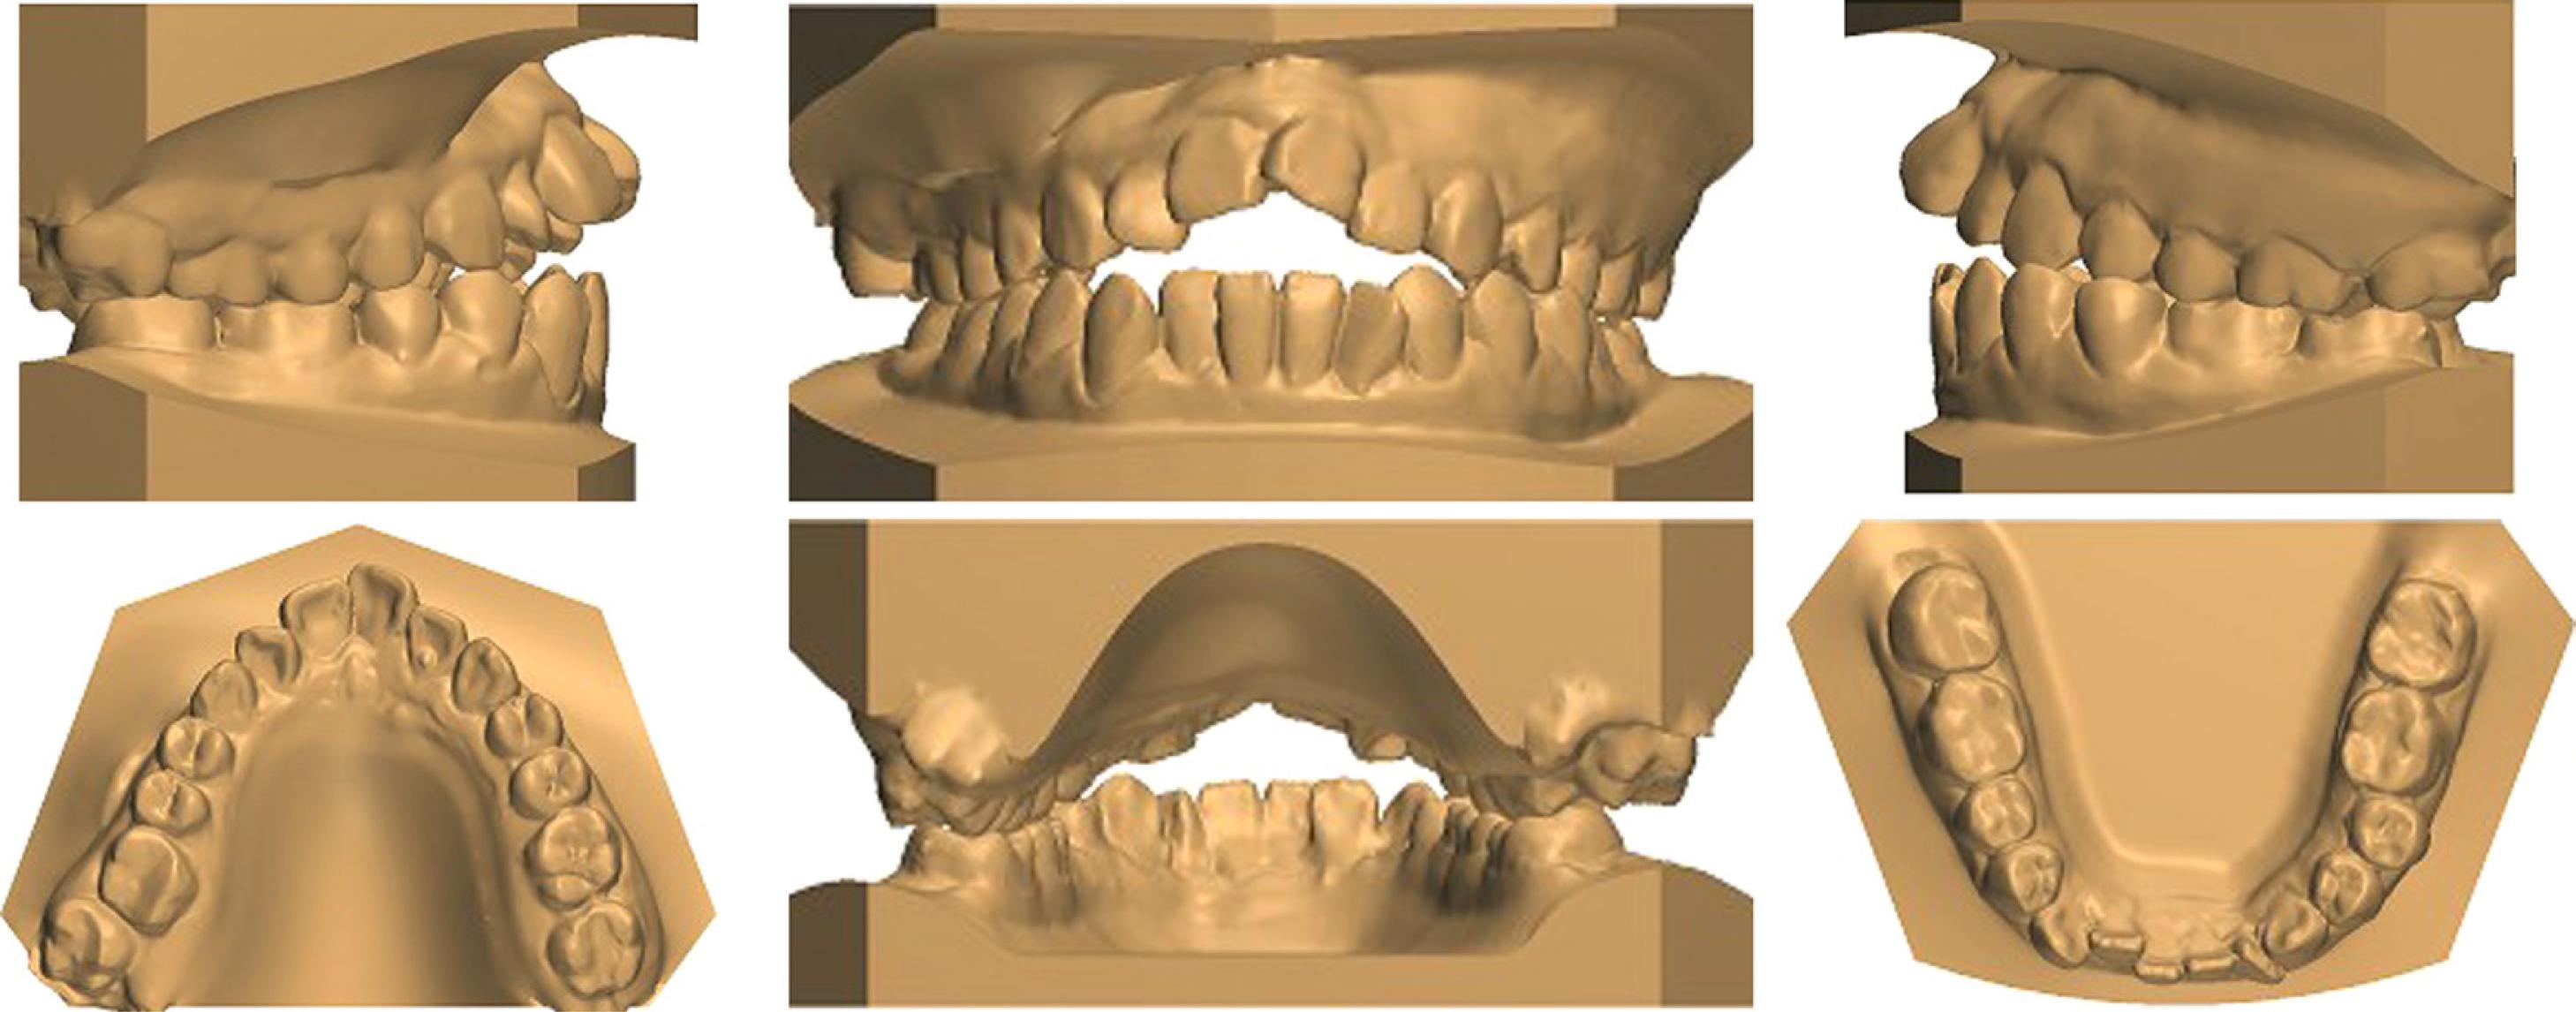

Figure 1.